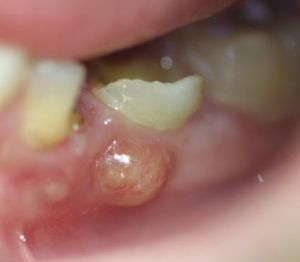

Tályog a szájban – képek

A tályog a szájban képek forrása a Wikipédia.